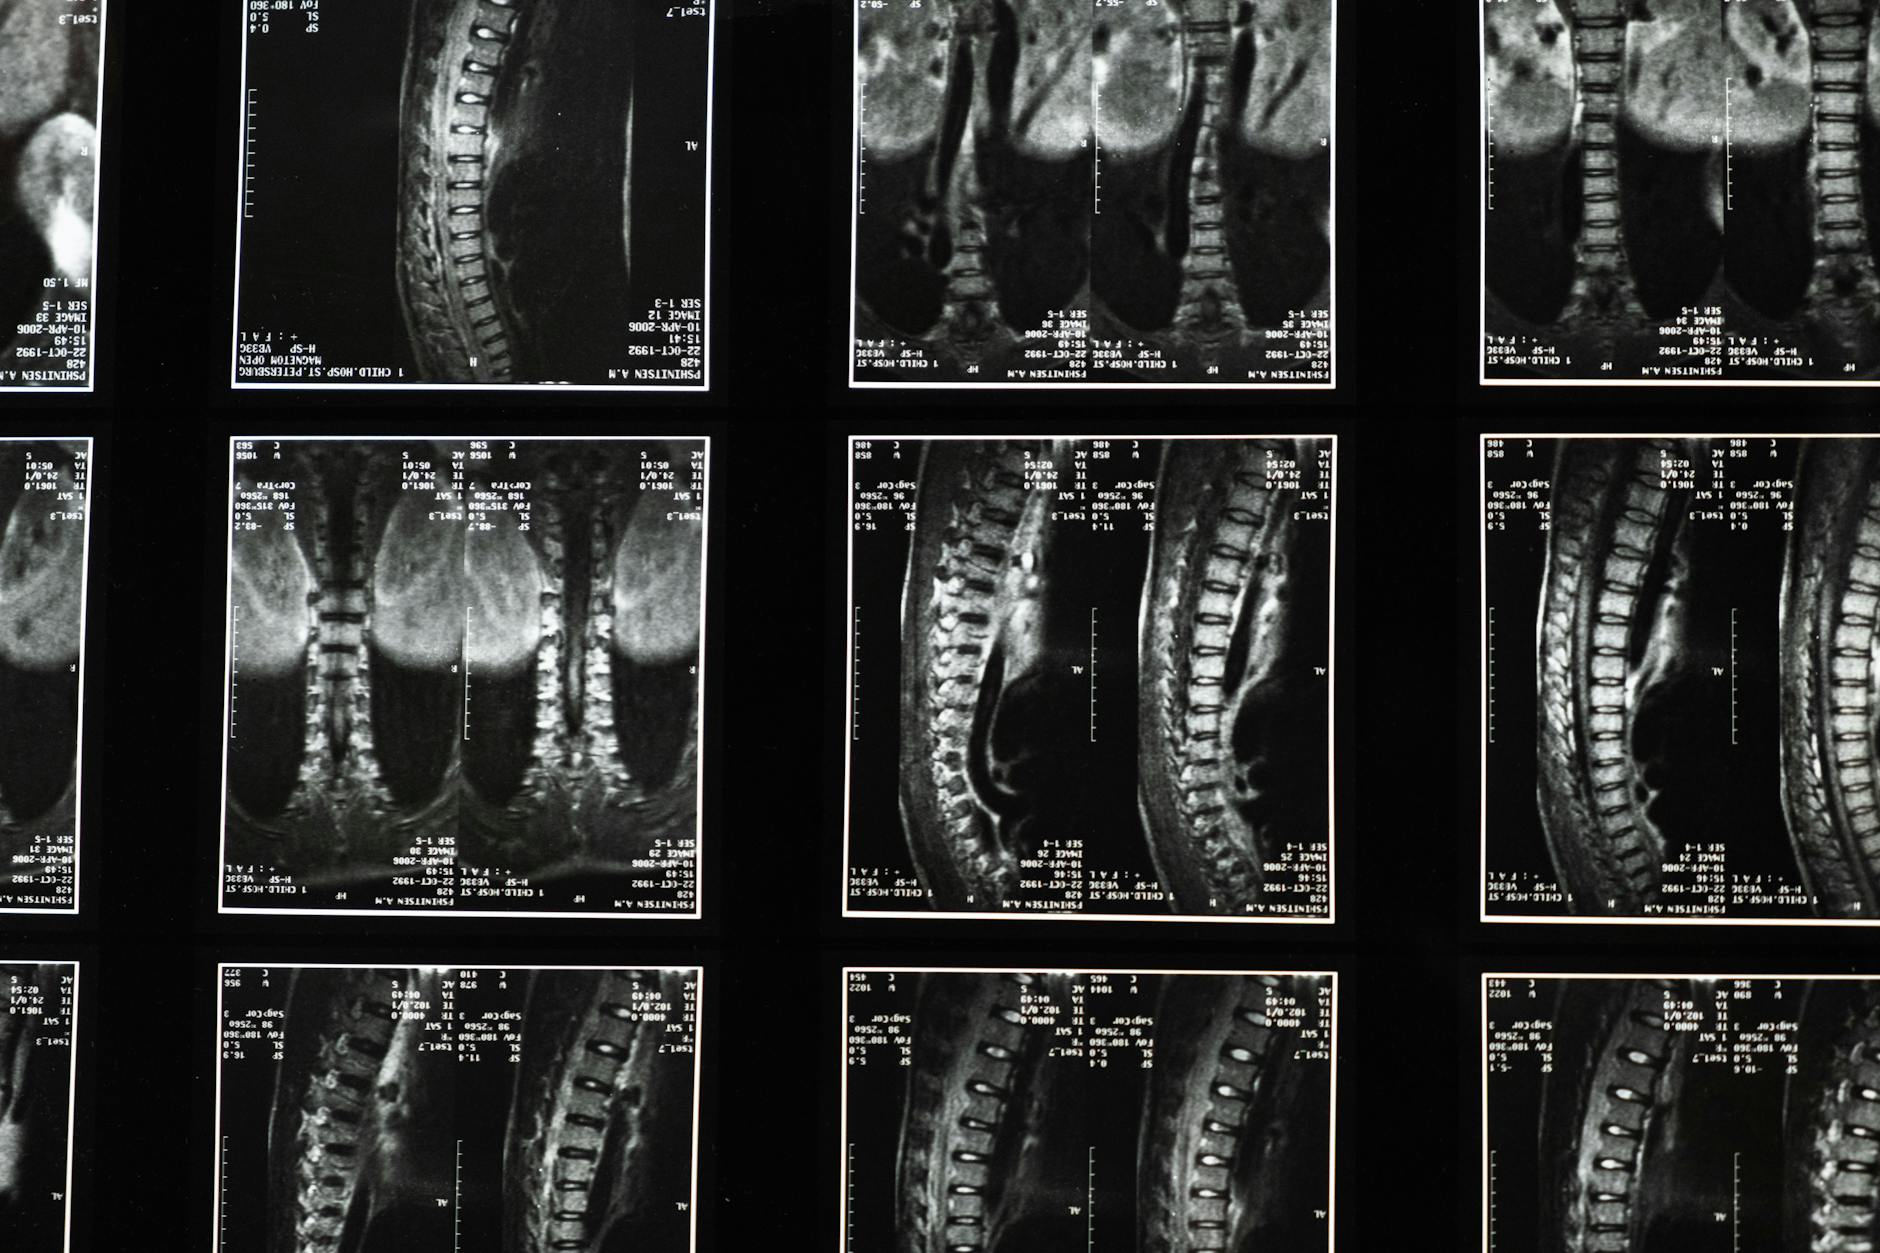

Here’s an important limitation to understand: many people have bulging or even herniated discs visible on imaging (MRI or CT scans) but experience zero pain. More than 3 million Americans per year experience symptomatic herniated discs, but imaging studies show that bulging discs are incredibly common in people without any back pain at all. This means that imaging findings don’t always correlate with symptoms, and a “bulging disc” seen on imaging isn’t automatically a disaster—most bulging discs never become symptomatic or cause progressive damage. The reverse is also true: if your pain is severe, don’t assume imaging will show a corresponding disc problem. Significant pain can exist with minimal imaging findings, especially in the early inflammatory phase of a disc injury.